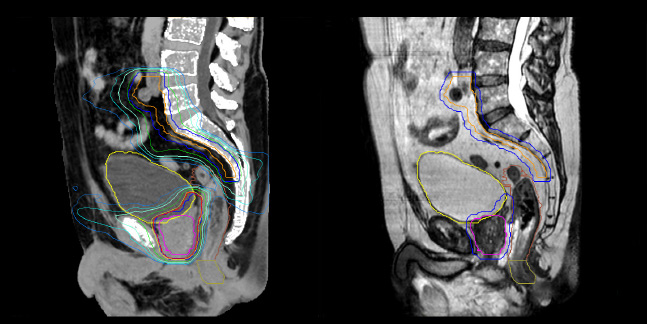

Comparison of CT simulation scan

Comparison of CT simulation scan (left) and T2W 3D MRI (right)

MR-based contouring and planning

MR based target contouring

MR-based target contouring on 3D T2W TSE in transversal, sagittal

and coronal planes.

Personalized VMAT dose

Personalized VMAT dose planned in Philips Pinnacle.

Evaluation of MRCAT dosimetric accuracy

Dosimetric equivalence validation was performed on 43 patient cases by comparing MRCAT-based dose plans overlaid on CBCT image dataset and on the corresponding MRCAT image dataset. Mr. Bolard and Dr. Champion found good agreement between MRCAT-based and CT-based dose calculations, with a mean dose ratio of 1.007 (0.991-1.014). The 3D gamma score was greater than 95% (95.2-99.0%) for all plans checked. A poster on this work was accepted for presentation at ESTRO 2020.

Dataset MRCAT image

Dose plans overlaid on CBCT image dataset (left) and on MRCAT image dataset (right).